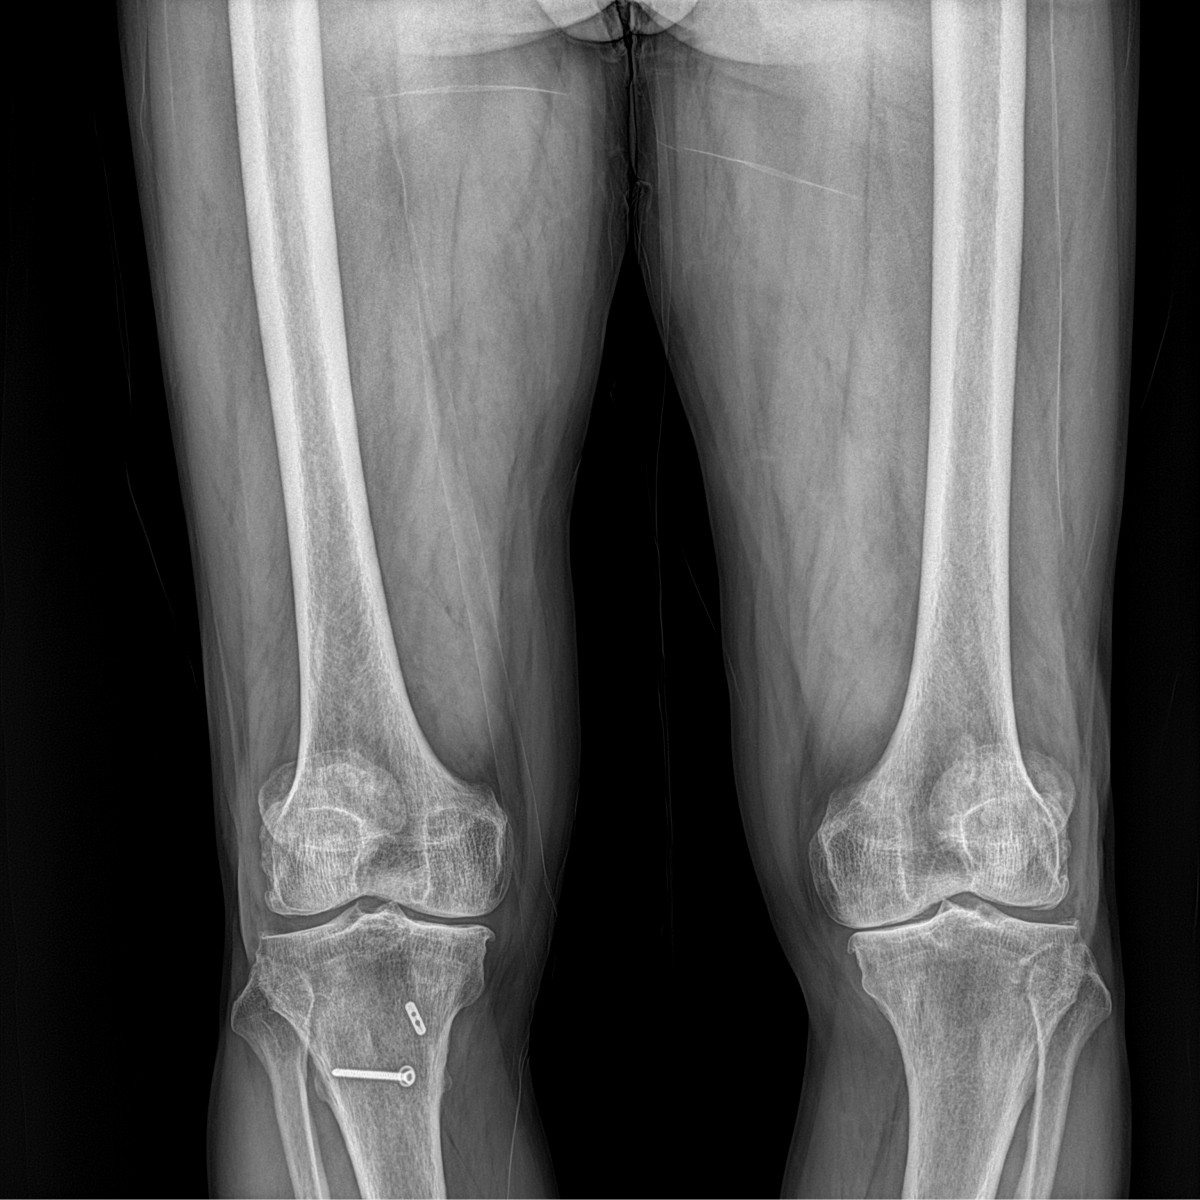

이재상원장님 무릎 인공관절 치환술 박용O 환자

dae765e4d9ac96aee867c9d6292d8784_1758010003_5618.jpg